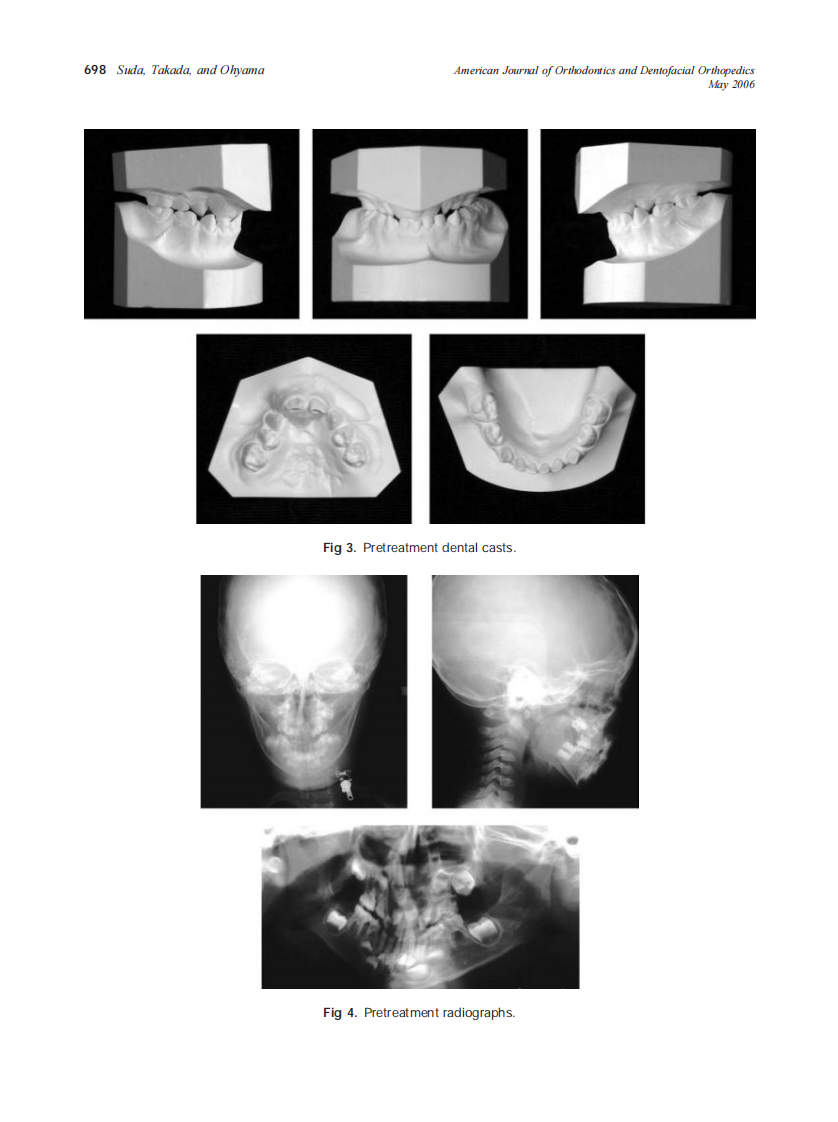

AJO-DO

2006_129_5_696_705_Suda.pdf